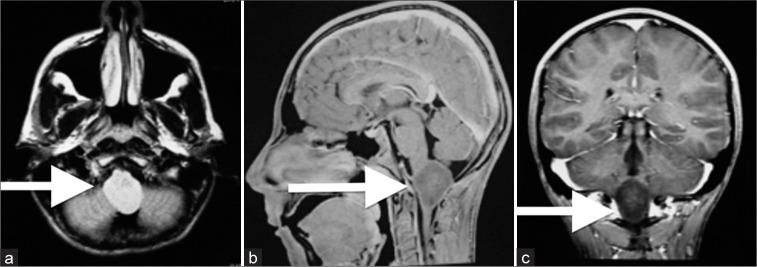

In this case report, the authors describe a 28-year-old male from Saudi Arabia who presented with headaches and vomiting. Imaging studies and clinical examination revealed a high-grade astrocytoma medullary brainstem lesion. The patient underwent radiation therapy and chemotherapy, effectively controlling tumor growth and improving his quality of life. However, a residual tumor remained, and the patient underwent neurosurgery to resect the remaining tumor was successful in removing the tumor, and the patient showed significant improvement in his symptoms and overall health.